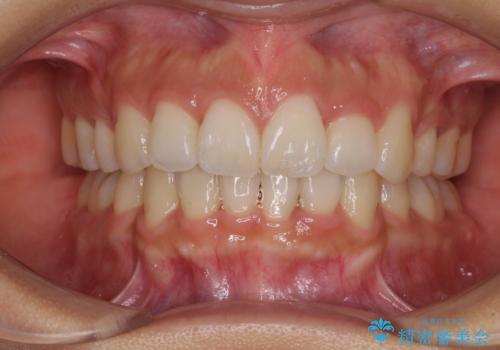

インビザラインは、装着していない時間がどれだけ短いかが、治療期間を大きく左右します。こちらの患者様は1日22時間以上、毎日欠かさず装着してくださったため、1年弱という短期間で満足のいく歯列に整えることができました。